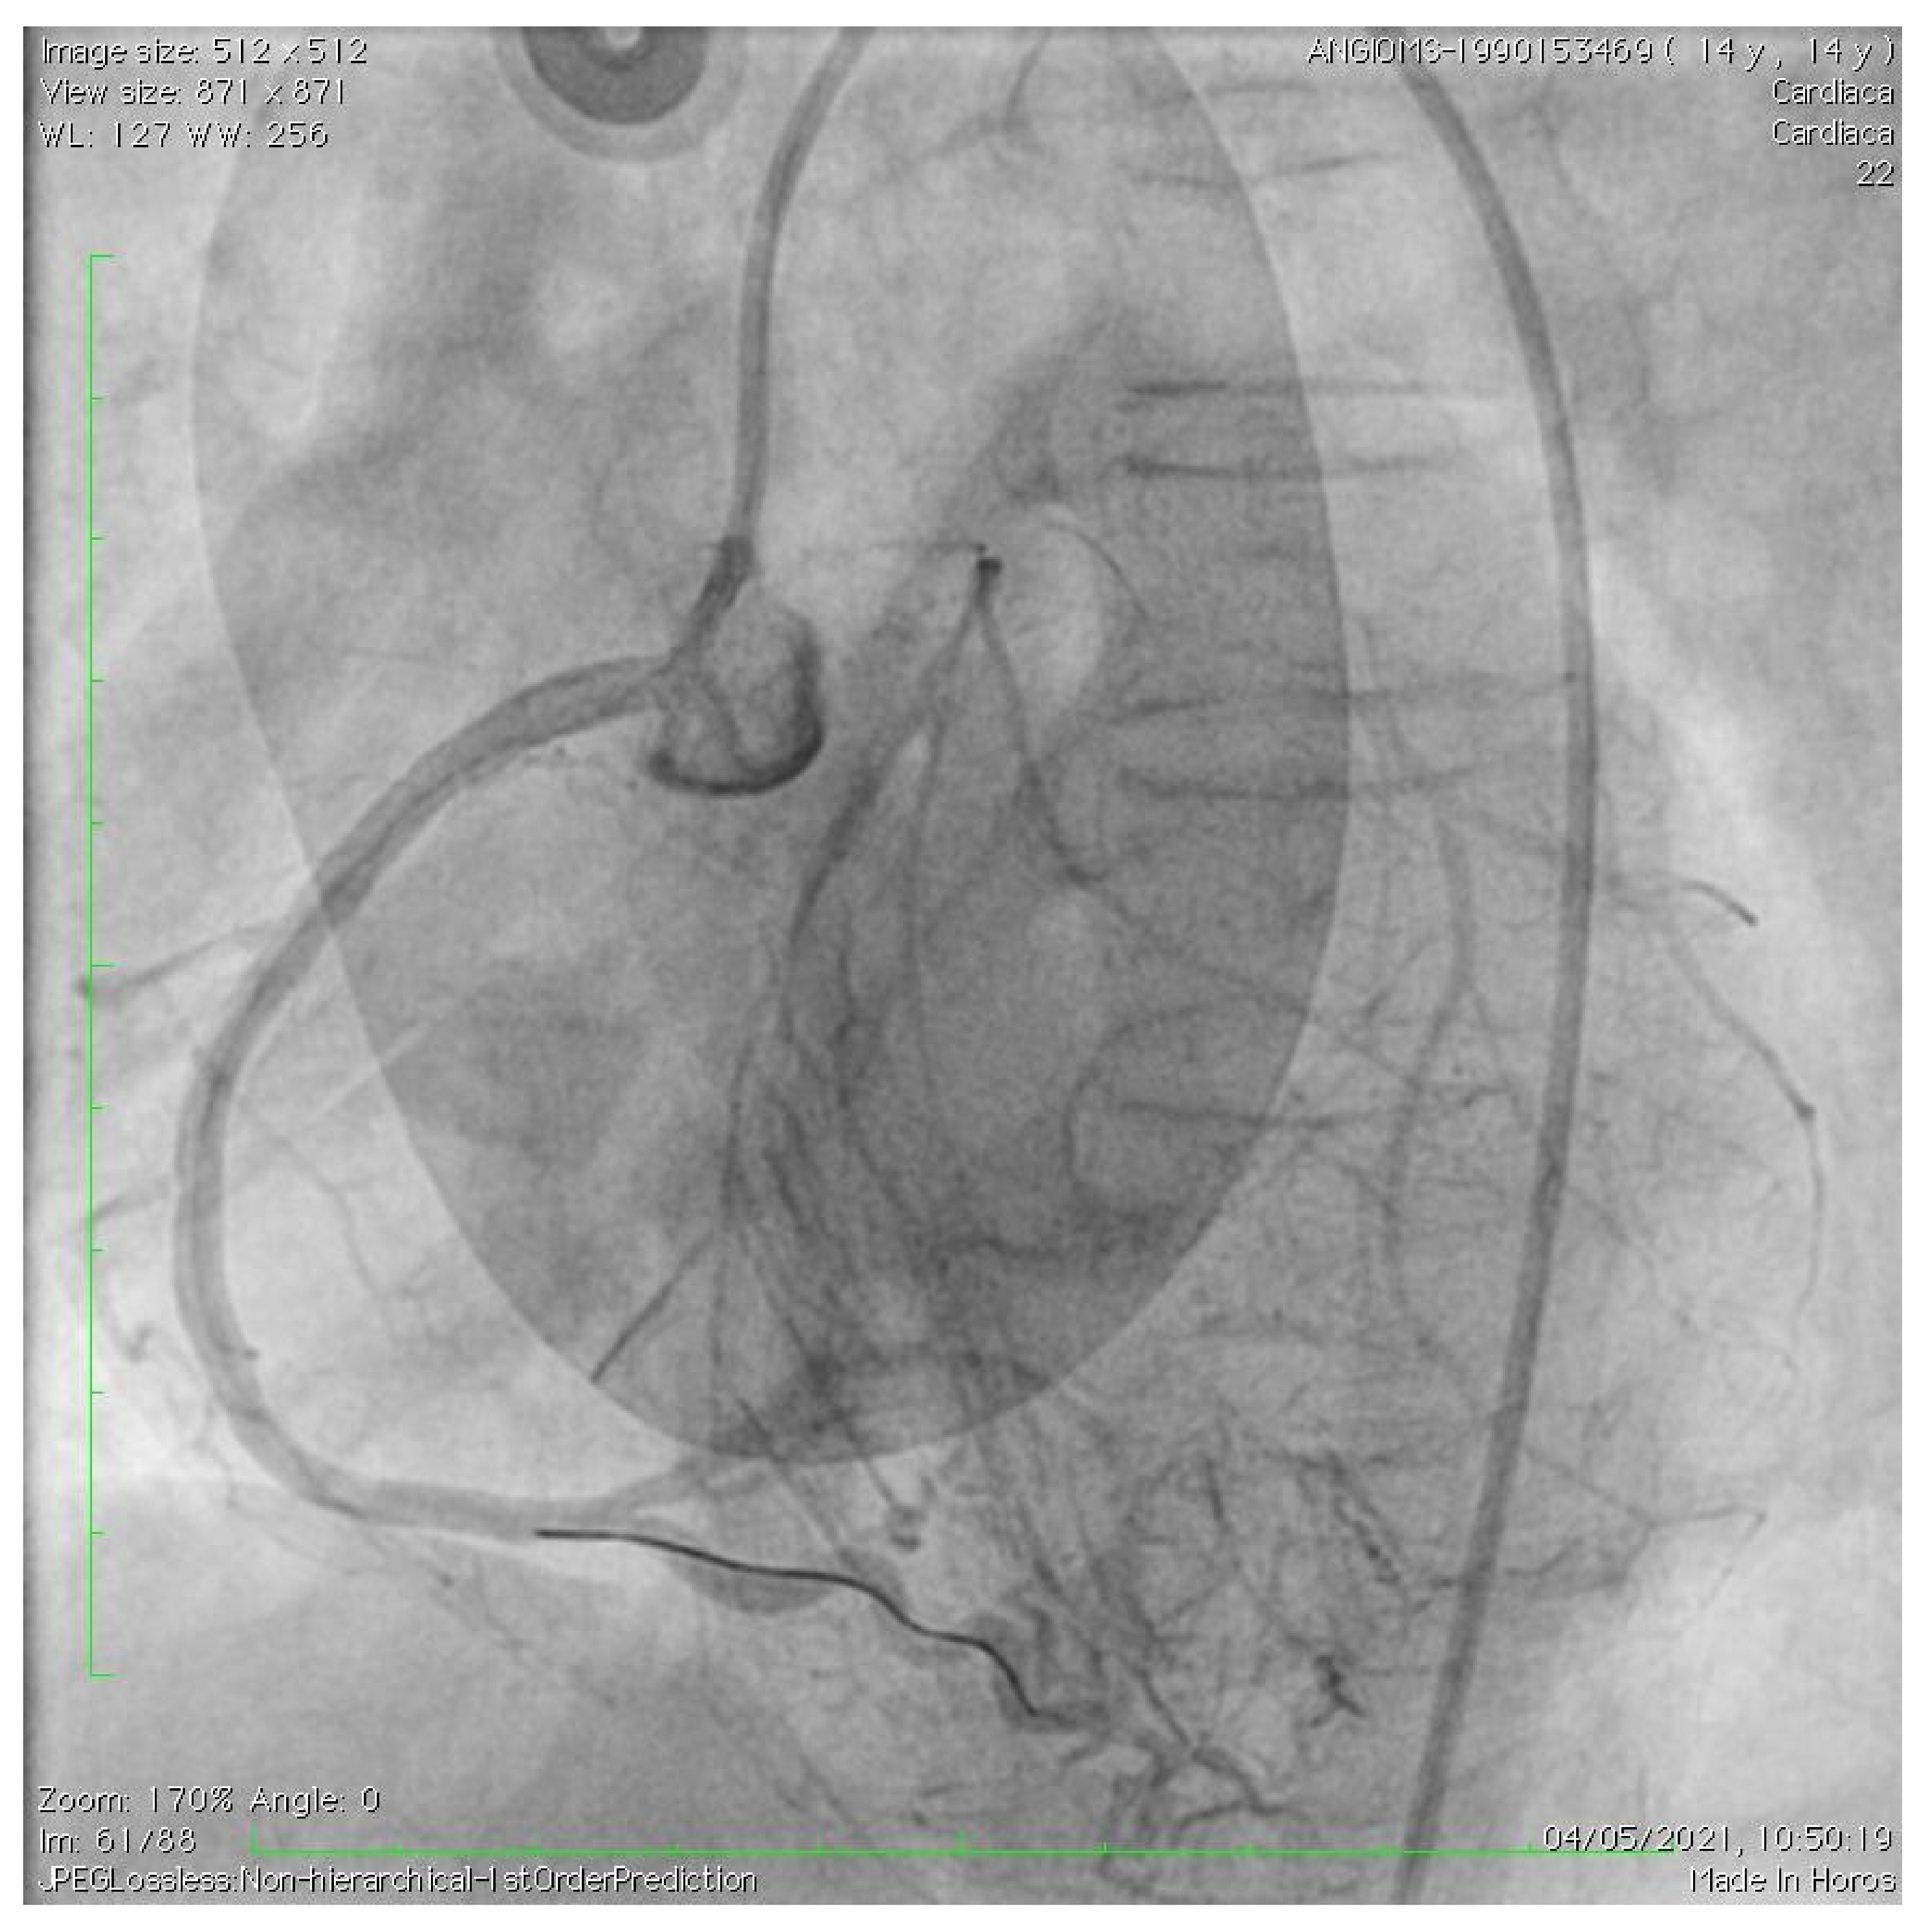

2. Case Description

- Roggen, M.; Dubois, C.; Gewillig, M. Coronary artery stenting in a patient with progeria. Catheter. Cardiovasc. Interv. 2017, 90, E38–E40. [Google Scholar] [CrossRef] [PubMed]

- Callahan, R.; Lock, J.E.; Shah, P.B.; Marshall, A.C. Transcatheter intervention of coronary ob structions in infants, children and young adults. Pediatr. Cardiol. 2018, 39, 1299–1307. [Google Scholar] [CrossRef]